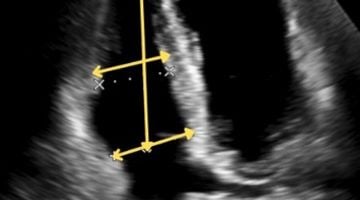

We connect a broad community of sonographers and clinicians who utilise cardiac ultrasound in the echo lab, the intensive care, the operating room, the emergency room and point-of-care.